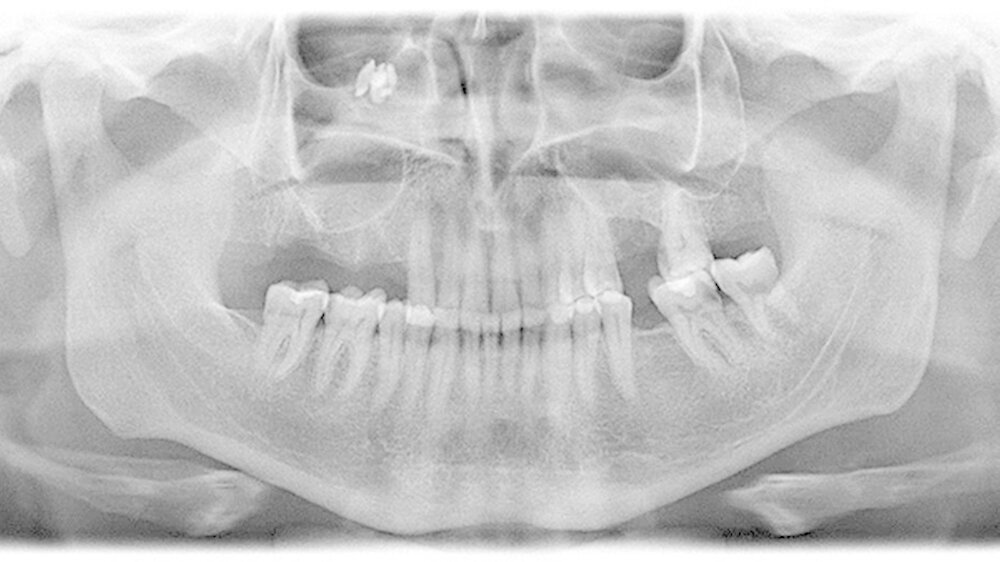

Das angefertigte Orthopantomogramm (OPT) stellte den aktuellen Zahnstatus mit dem Nebenbefund einer röntgendichten Verschattung im Sinne eines Fremdkörpers unterhalb des rechten Kieferhöhlendachs dar (Abbildung 1). Es folgte die Anfertigung eines NNH-CT zur genauen Lokalisierung des Fremdkörpers (Abbildung 2) für die anschließende OP-Planung.

In unserem Fall zeigte sich der röntgenopake Fremdkörper im OPT als Zufallsbefund. Zur genauen Lokalisation ist jedoch eine zwei- bis dreidimensionale radiologische Darstellung notwendig [Ferguson, 2014]. Bei der zweidimensionalen Darstellung bietet sich zum OPT ein Fernröntgenseitenbild und bei der dreidimensionalen ein DVT, NNH-CT sowie im Fall von nicht ferromagnetischen Fremdkörpern auch ein MRT an.